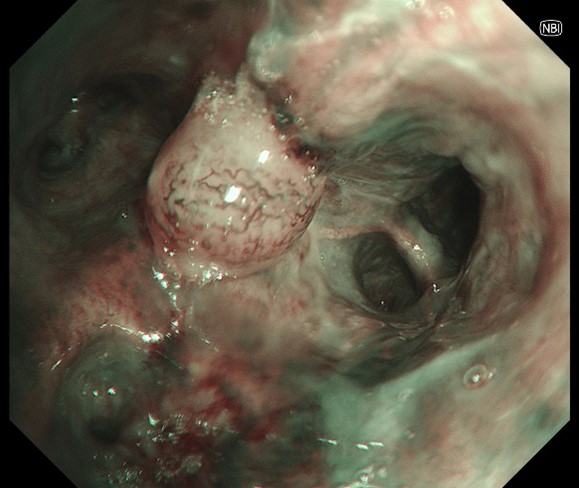

2-1. NBI

New tumor nodule over LC (between LB1+2 & LB3). NBI showed significant neo-vascularization, but the lack of deeper mucosal vessels on RDI over the central part of the nodule help assure that EBBX is safe.